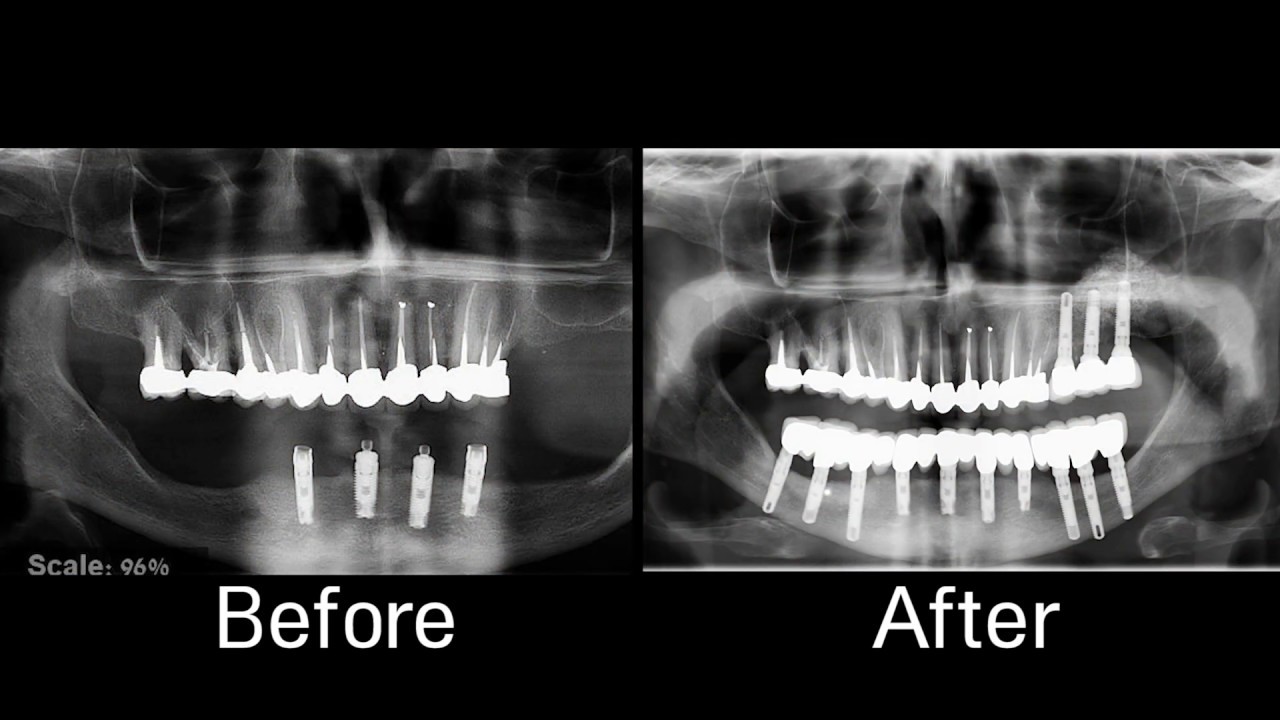

From implantpracticeus.com

Implant CE Article Surgery in prevention of inferior alveolar nerve Alveolar Nerve Damage Treatment Randomised controlled trials (rcts) involving interventions to treat patients with neurosensory defect of the. In this review we present algorithms to guide the clinical management of patients who sustain damage to the inferior alveolar or lingual nerves during the removal of lower third. Inferior alveolar branch of the trigeminal nerve is the most commonly injured branch, followed by the lingual. Alveolar Nerve Damage Treatment.

Implant CE Article Surgery in prevention of inferior alveolar nerve Alveolar Nerve Damage Treatment Inferior alveolar branch of the trigeminal nerve is the most commonly injured branch, followed by the lingual nerve. In this review we present algorithms to guide the clinical management of patients who sustain damage to the inferior alveolar or lingual nerves during the removal of lower third. There is a range of common inferior alveolar nerve damage symptoms, regardless of. Alveolar Nerve Damage Treatment.

Implant CE Article Surgery in prevention of inferior alveolar nerve Alveolar Nerve Damage Treatment In this review we present algorithms to guide the clinical management of patients who sustain damage to the inferior alveolar or lingual nerves during the removal of lower third. There is a range of common inferior alveolar nerve damage symptoms, regardless of how the ian is damaged. Damage to either nerve can lead to numbness and pain of the lip,. Alveolar Nerve Damage Treatment.